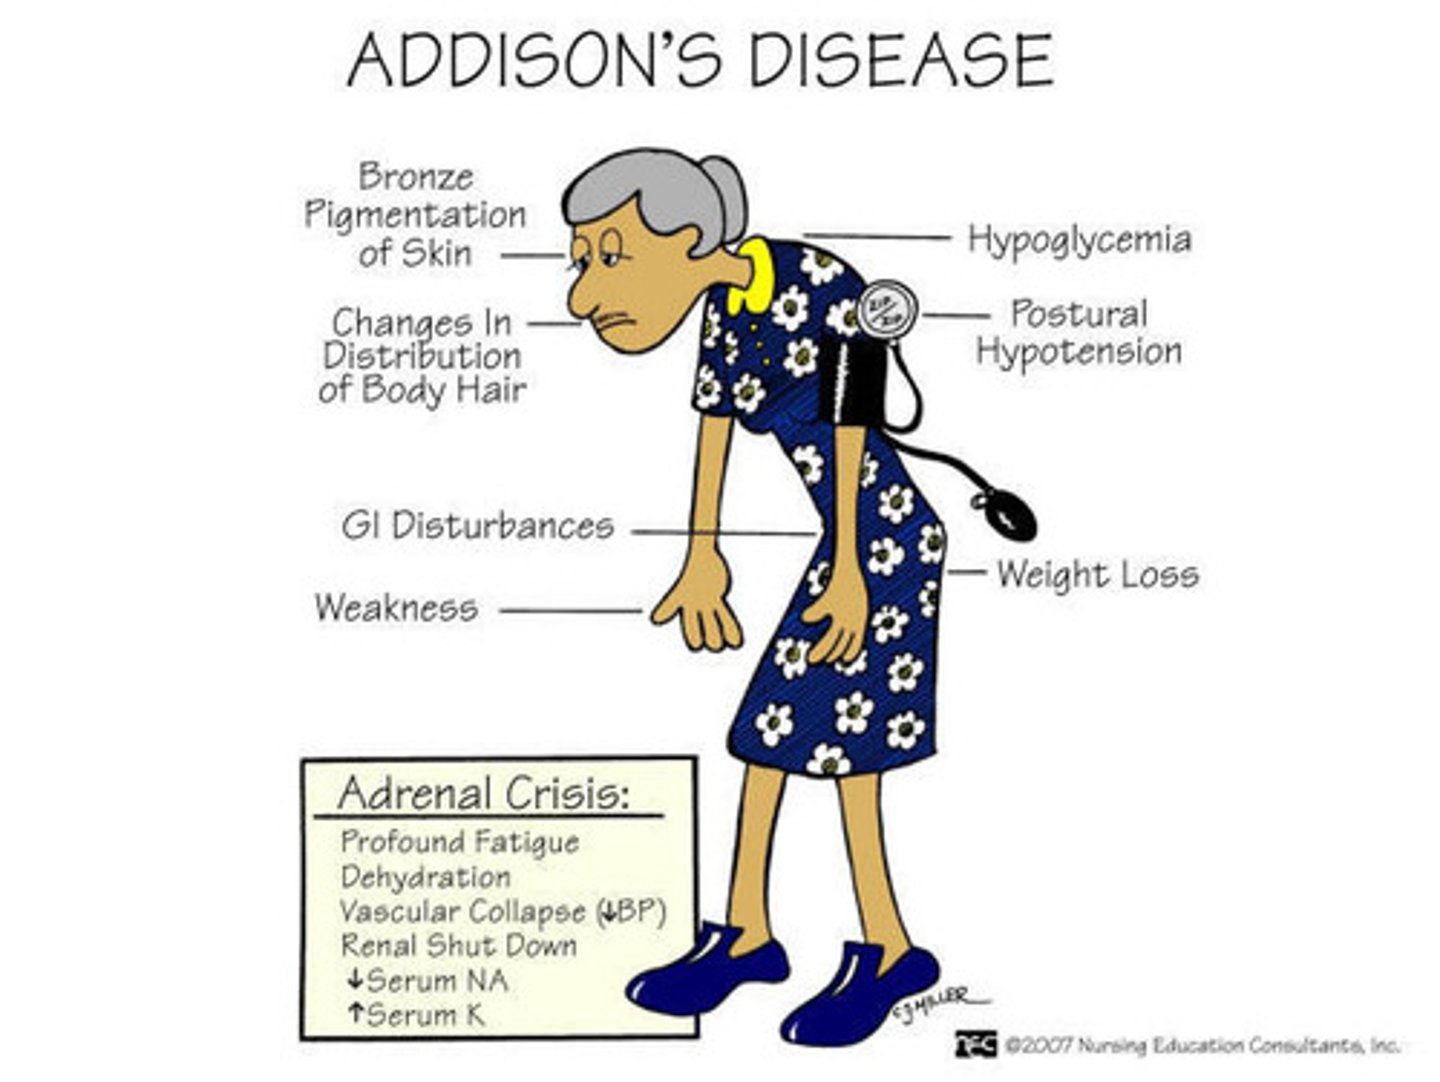

Skin hyperpigmentation, hypotension, fatigue

Primary Adrenocortical insufficiency (e.g., Addison disease) causes increased ACTH and increased alpha-MSH production (skin pigment from POMC)

TB is most common cause in developing